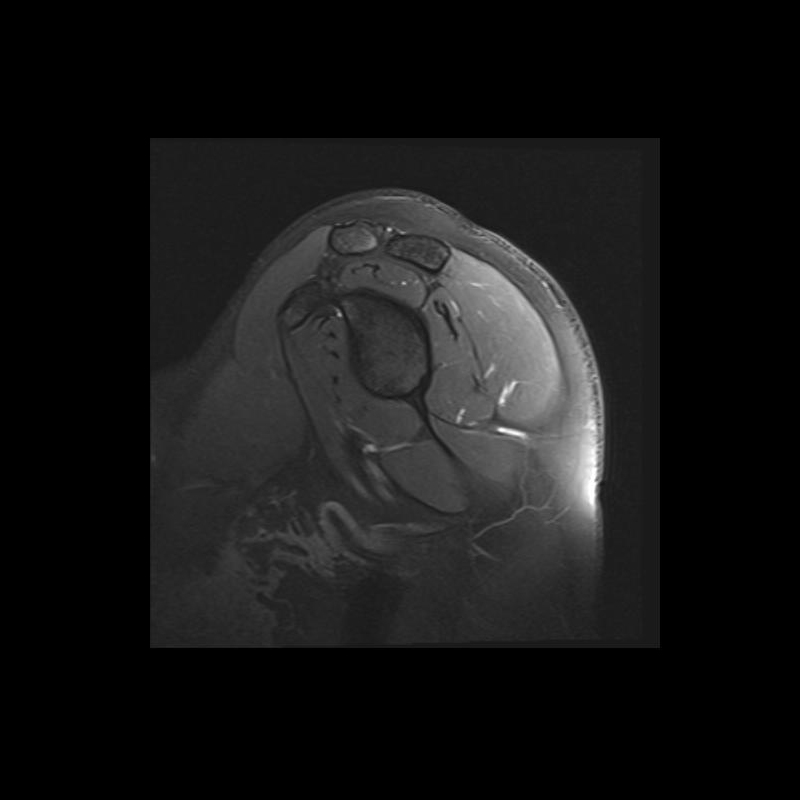

Shoulder MRI Anatomy